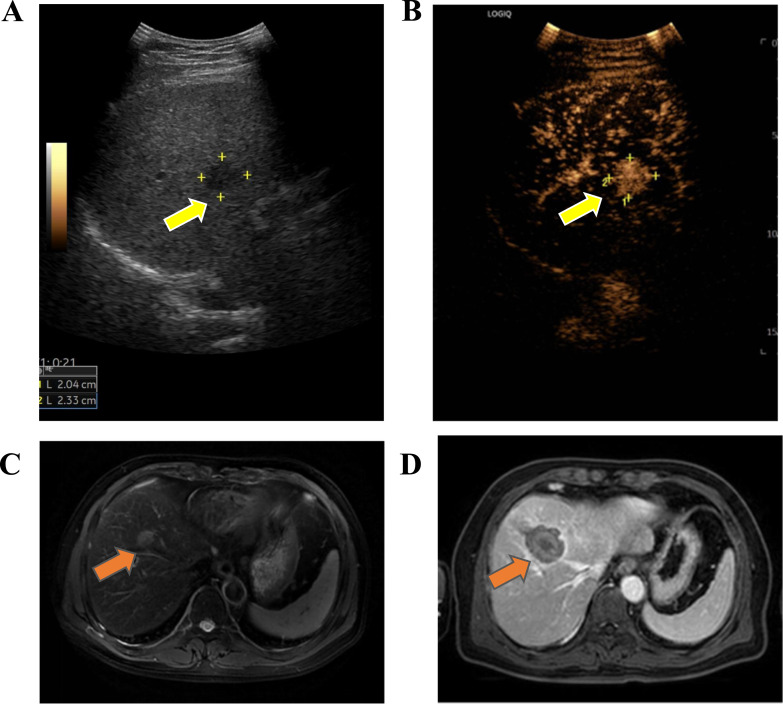

目的建立一种预后模型,以优化不同原发肿瘤部位行热消融(TA)的结直肠癌肝寡转移(CLOM)患者的预后管理。材料和方法本回顾性研究的报告符合STROBE指南。在2011年至2021年期间,共有525名来自3家医院的CLOM患者接受了TA。首先,分析不同原发肿瘤部位的CLOM患者肝内、肝外无病生存期(DFS)和总生存期(OS)。然后,使用cox回归模型识别预测OS的独立因素。最后,制定了预后评分来确定从TA中获益的CLOM患者。所有患者的详细信息都被删除了。结果共纳入423例符合条件的患者,其中CLOM患者762例(男性121例,中位年龄59岁),中位随访45.8个月(IQR, 7.3 ~ 114.8)。确定了OS的独立预测因子,包括多发性肝转移(P = 0.0085)、右侧结肠癌(P = 0.0210)、肿瘤大小≥2 cm (P = 0.0273)和原发性结直肠癌淋巴结转移(P = 0.0302),称为“MRSL”评分。在MRSL评分最佳分离的基础上,将患者分为高危组(临界值≥8)和低危组(临界值P = 0.0156)。而低危组左、右侧CLOM患者的OS无显著差异(97.7 vs 102.2个月,P = 0.28)。结论基于MRSL评分的模型有助于选择受益于TA的潜在右侧clm患者。

ObjectiveTo develop a prognostic model for optimizing management of colorectal liver oligometastases (CLOM) patients with different primary tumor locations who underwent thermal ablation (TA).Materials and MethodsThe reporting of this retrospective study conforms to STROBE guidelines. A total of 525 CLOM patients who underwent TA from 3 hospitals between 2011 and 2021 were enrolled. Firstly, intra and extrahepatic disease-free survival (DFS) and overall survival (OS) for CLOM patients with different primary tumor locations were analyzed. Then, cox regression models were used to identify independent factors predicting OS. Finally, a prognostic score was developed to identify CLOM patients benefiting from TA. All patient details were de-identified.ResultsA total of 423 eligible patients were identified, with 762 CLOM (121 male, median age 59 years) and a median follow-up of 45.8 (IQR, 7.3-114.8) months. Independent predictors of OS were identified, including multiple liver metastases (P = .0085), right-sided colon cancer (P = .0210), tumor size ≥2 cm (P = .0273), and lymph node metastasis of primary colorectal cancer (P = .0302), termed as the "MRSL" score. On the basis of the best separation of MRSL score, patients were divided into high-risk (cutoff value ≥8) and low-risk groups (cutoff value <8). Further stratified analysis indicated that right-sided CLOM patients had shorter OS than left-sided patients in the high-risk group (54.9 vs 92.5 months, P = .0156). However, no significant difference in OS was observed between right-sided and left-sided CLOM patients in the low-risk group (97.7 vs 102.2 months, P = .28).ConclusionThe MRSL score-based model helps in selecting potential right-sided CLOM patients who benefit from TA.